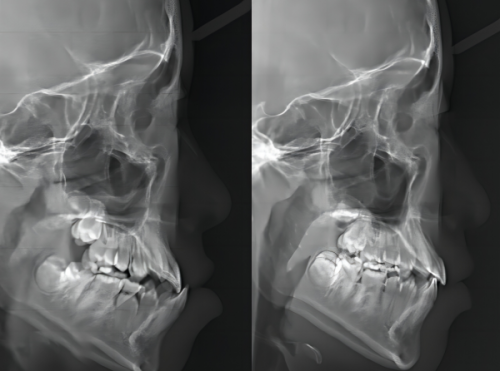

技术方面,成都新桥口腔目前注册医生200余名,其中包含多名华 西技术人才,他们不仅亲和力强,而且医术高明,能够根据患者的困扰快速找到问题所在,并制定出合理的方案进行治疗。尤其是对于种植牙和牙齿矫正项目,成都新桥口腔掌握有大量的临床成功数据,目前正畸实例3W +,种植牙实例10W +。除了常规的治疗技术外,他们也攻克了多项高难度手术,有牙齿问题的可以放心选择。收费上,作为一家有着多年经验的高品质牙科,成都新桥口腔在收费方面是严格按照卫生局标准执行的,收费公正合理透明,没有隐形消费,不用担心会有多收费或乱收费现象。

绝活上,在牙齿矫正和牙齿种植领域,新桥口腔在整个西部地区都是佼佼者,它是“隐适美”“时代天使”等大牌隐形矫正版牌以及“士卓曼”“诺贝尔”等高端种植体品牌的临床示范基地。医生团队上,新桥口腔有将近200名口腔医生,都是国内有名口腔院校毕业的精英,各个专科还有华 西口腔的骨干医生坐镇,技术水平完全不用担心。